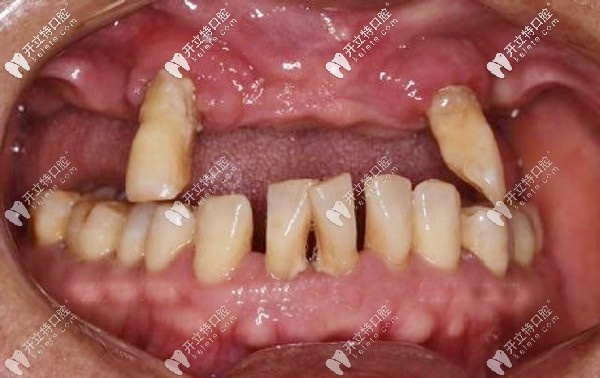

周老先生十多年前先后缺失了三四顆牙后鄰牙就開(kāi)始晃動(dòng),直到今年年初,上頜的牙齒只剩下兩顆,吃飯也受到影響才去牙科看牙。

“很多老人口腔情況跟我一樣,覺(jué)得掉牙不是什么事兒,即使旁邊的牙松動(dòng)了,也是能拖就拖,疼了就吃點(diǎn)消炎藥,誰(shuí)知道這樣一拖問(wèn)題”

周老先生后悔地說(shuō),自己年輕的時(shí)候就是太輕視缺牙,沒(méi)有及時(shí)修復(fù),才導(dǎo)致現(xiàn)在的牙齒松動(dòng),東西都得拿手掰著吃,根本不敢拿牙咬。